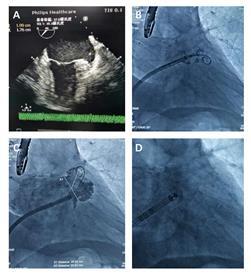

患者男性,60岁,房颤病史10余年,高血压2级,既往陈旧性脑梗,并发脑出血在当地医院行开颅去骨瓣减压术。今日在我中心行全麻左心耳封堵术,术中食道超声评估发现左心耳开口有新鲜血栓形成,经5000u肝素抗凝后有所好转,继续行封堵治疗,手术过程顺利(可见下图),释放27号左心耳封堵伞,病人安返病房。